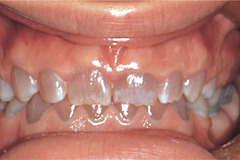

amelogenesis imperfecta

Front

Back